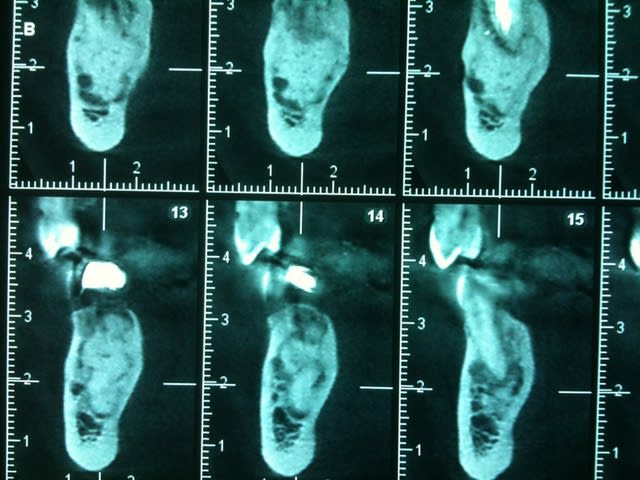

Un confrère savant pourrait il me donner un diagnostic et une CAT concernant le tissu osseux en regard de 45 ?

La racine parait fracturée mais à part une légère douleur à la pression, rien d'autre..

çà semble être une ostéïte condensante...